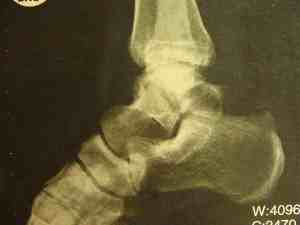

A forty year-old man fell about three metres, with immediate severe pain in the right foot. Within a short period the lower leg was oedematous and throbbing. He was unable to stand on the leg.

X-rays of the ankle were declared normal. Here they are.

Normal X-rays?

He was diagnosed with a bad sprain of the ankle, and put into a boot to limit movement.

Fractures in the ankle are notoriously difficult to see because of the overlapping structures. A scan revealed the partially healed fracture through the talus bone.

Worse, because of the disrupted blood supply to the talus, the main bone joining the leg to the foot is dying. A process called "avascular necrosis."

Can you see the great holes of dead bone in the talus? The fracture cut off the blood supply to the osteoblasts. It should have been pinned immediately.

How reliable are X-rays? Sometimes fractures can only be seen on a scan.